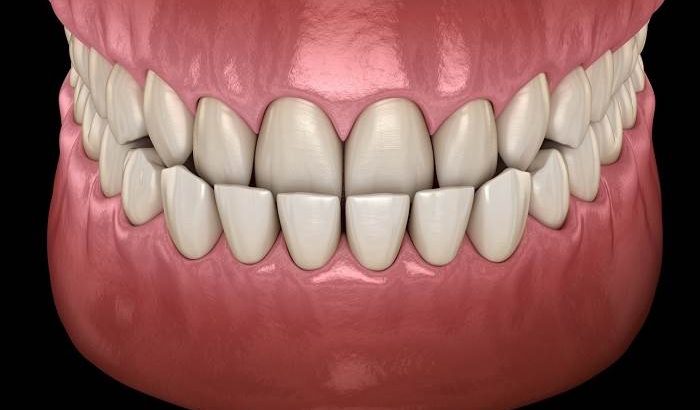

آندربایت یا عقب بودن فک بالا یک مشکل دندانی است که در آن دندانهای پایین جلوتر از دندانهای بالایی قرار میگیرند. این شرایط در کلاس III مال اکلوژن قرار میگیرد و باعث درد و ناراحتی فرد نیز میشود. حتی بسیاری از افراد دچار این مسئله، از این شرایط عقب بودن فک بالای خود خجالت میکشند که این امر بر سطح اعتمادبهنفس آنها تأثیر میگذارد.

برخی از موارد عقب بودن فک بالا، خفیف و تقریباً غیر قابل مشاهده است، درحالیکه موارد دیگر بسیار شدید هستند که در آنها دندانهای پایین خیلی جلو آمدهاند.